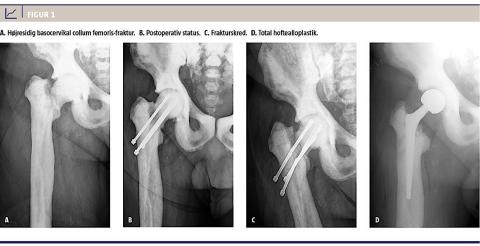

En 62-årig mand med AO og hofteartrose blev indlagt til osteosyntese med glideskrue pga. en højresidig

basocervikal collum femoris-fraktur. Ekstrem hård knoglekonsistens gjorde det imidlertid umuligt at bore gennem cortex med ledetråd, og derfor fravalgte man fiksering med glideskrue. Frakturen blev i stedet fikseret med tre kanylerede skruer. Det var dog også vanskeligt at forbore til skruer, og der blev til sidst anvendt et 6 mm-bor, som medførte suboptimal stabilitet. Et bor knækkede og måtte efterlades i collum. Det var heller ikke muligt at skære gevind, men skruerne blev fikseret i caput. Postoperative røntgenbilleder var tilfredsstillende, og patienten blev udskrevet efter et par dage.

Patienten blev langsomt mobiliseret med tiltagende belastning med klinisk og radiologisk kontrol hver 4.-6. uge. Fireogtyve uger postoperativt var der endnu ikke tegn på radiologisk heling, men der var klinisk fremgang med aftagende smerte. Det blev derfor vurderet, at frakturen var klinisk helet, og der blev påbegyndt genoptræning. Efter 52 uger havde han tiltagende smerter og nedsat gangfunktion. En røntgenoptagelse viste frakturskred og knækkede skruer (Figur 1).

Patienten blev nu tilbudt total hoftealloplastik. En CT viste en vertikal fissur forrest i acetabulum og minimal marvhule i femur. Operationen blev nøje planlagt med fremskaffelse af passende skærende værktøj. Under operationen blev der vejledt af gennemlysning og under anvendelse af highspeed-boremaskine med tungsten-carbid-bor og kuglefræser, friske bor i forskellig diametre og koniske reamere skabt plads til femurstemmet (Wagner CONE, Zimmer). Præpareringen af acetabulum var uproblematisk.

Der blev isat cementeret acetabulumkomponent (Durasul Low Profile, Zimmer).